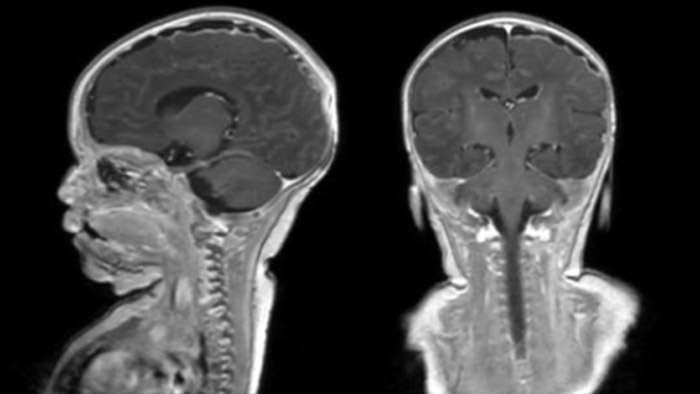

Hydrocephalus post hemorrhagic

Both pictures show a ventriculoperitoneal shunt. With our previous scanner our hydrocephalus protocol needed about 25 min. With Ambition the examination time is about 14 min. including a CSF PCA sequence to show flow in the aqueduct.